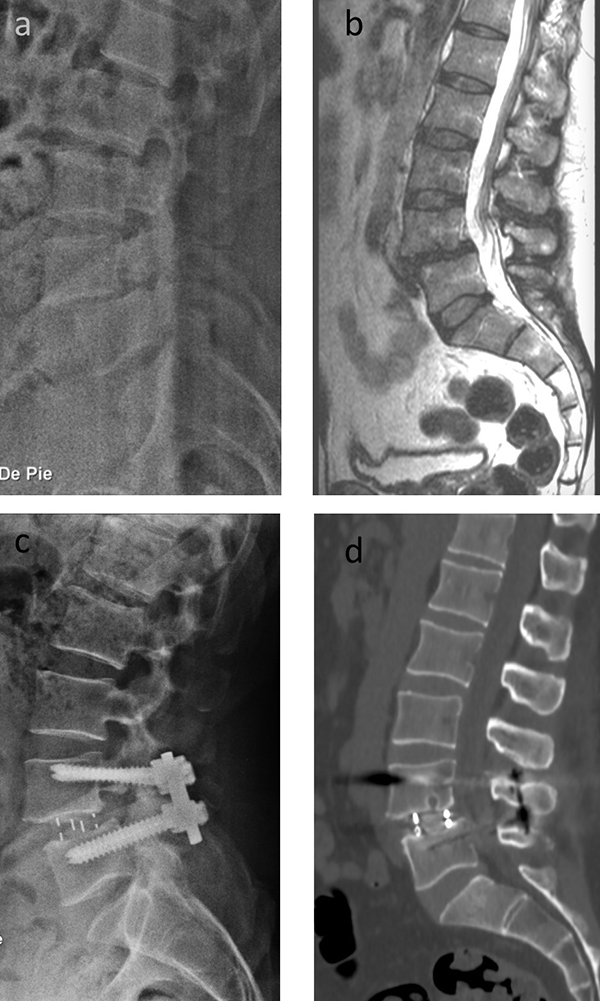

Figura 8: Imágenes pre (a y b) y postoperatorias (c y d) del paciente número 3. El mismo presentaba radiculopatía bilateral y claudicación neurógena de la marcha, asociado a dolor lumbar mecánico refractario al tratamiento conservador. Se realizó un OLIF L4-5 y una instrumentación posterior segmentaria por vía Wiltse.